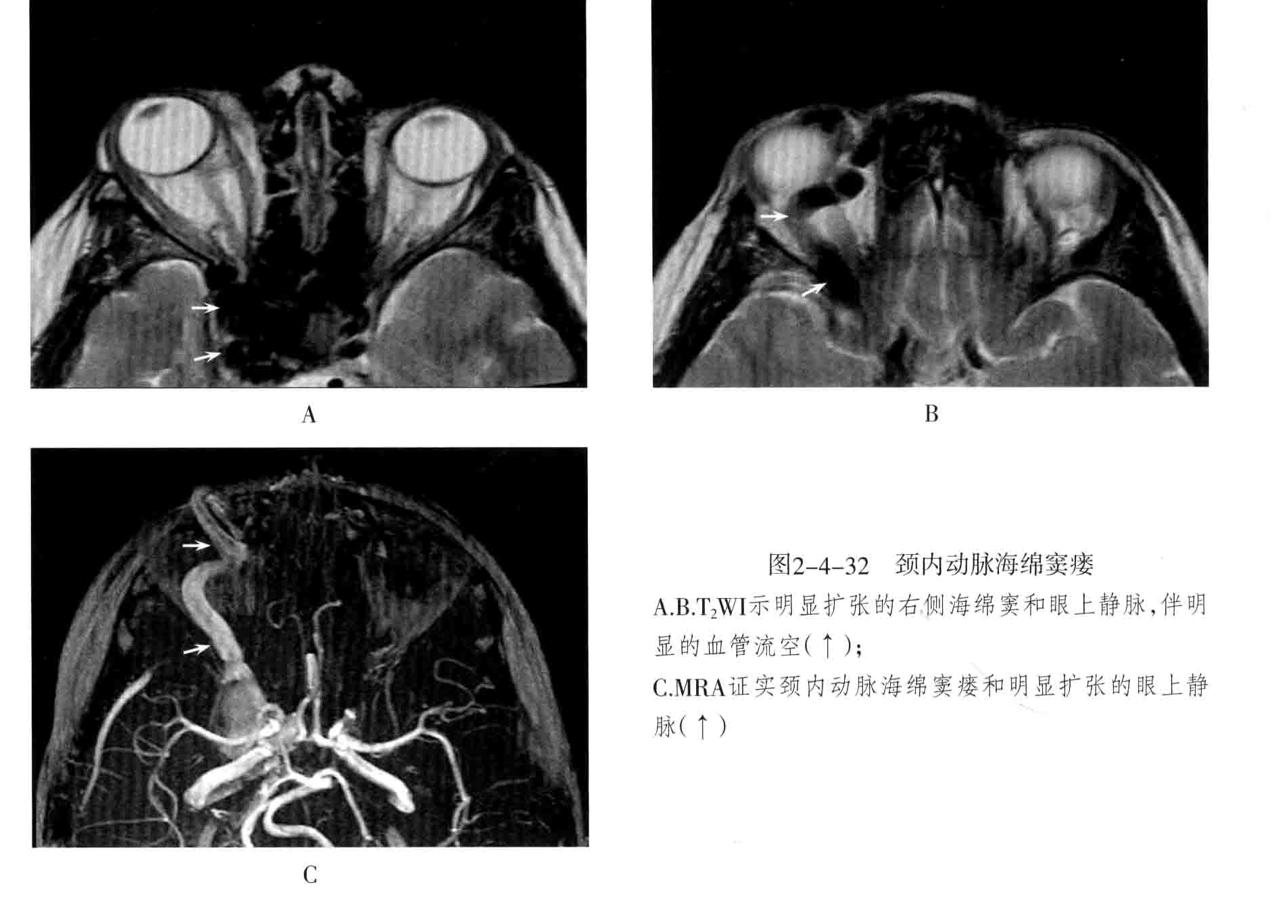

颈内动脉海绵窦瘘: 定义:指海绵窦段的颈内动脉及其分支破裂,与海绵窦之间形成动静脉的异常沟通所引起的一组神经眼科综合征。75%以上由外伤性引起,多为单侧发病,眼部征像多出现在患侧。

2. MRI:海绵窦扩大,海绵窦内血管影增多,且迂曲、粗大、不规则。同侧眼上静脉明显扩张,呈迂曲的流空信号。眼外肌增粗充血和眼球突出。需与海绵窦肿瘤性病变鉴别。